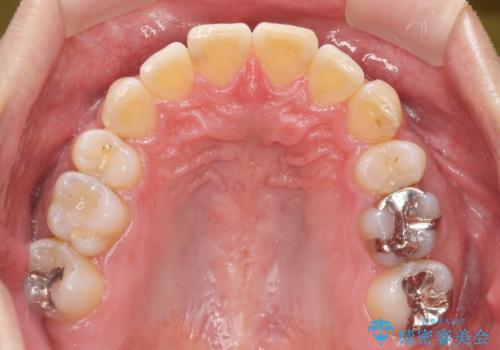

治療終了後、治療前後の写真をお見せすると「全然違いますね!」と喜んで下さいました。

実際の矯正期間は3ヶ月2週間(マウスピース14枚、1週間交換)と短期間で治療を終えることができました。

装置の種類:インビザライン ライト